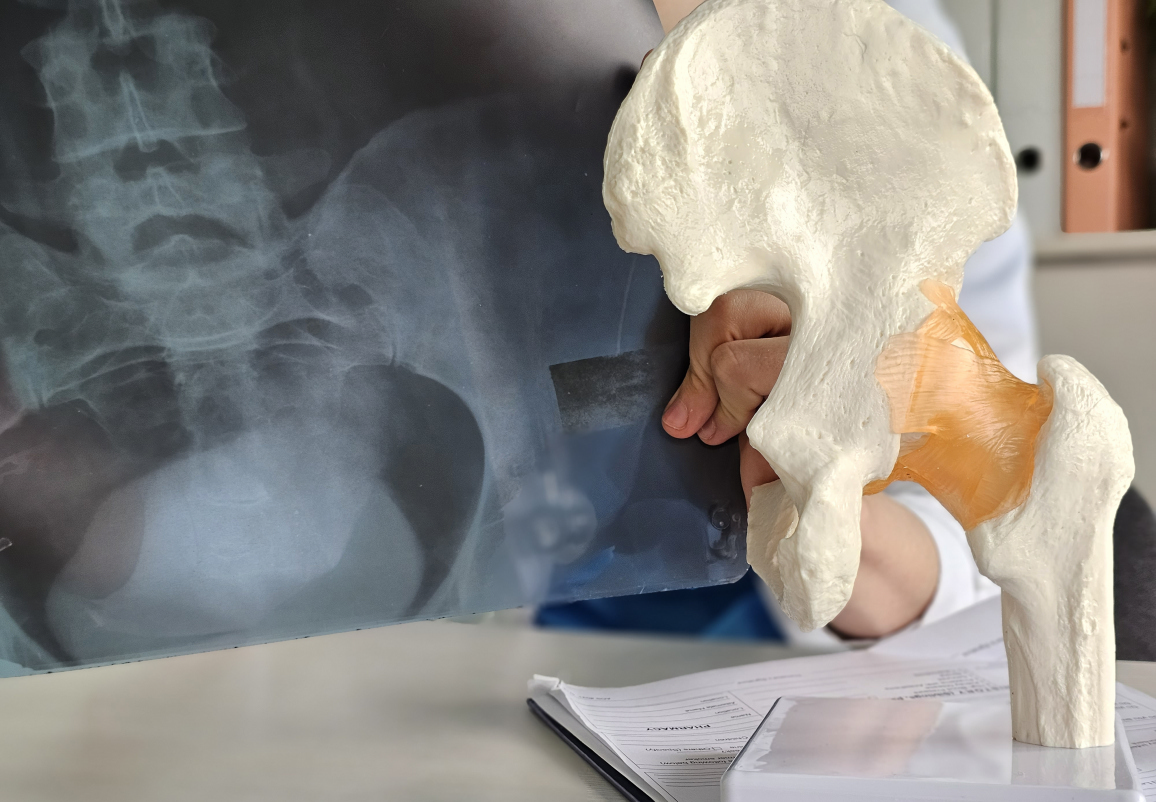

Диагностика перелома бедра

Для диагностики переломов бедра используется несколько методов:

- Рентгенография — основной метод визуализации для подтверждения и определения типа повреждения.

- КТ и МРТ — используются для уточнения диагноза, особенно при сложных повреждениях и повреждениях суставов.